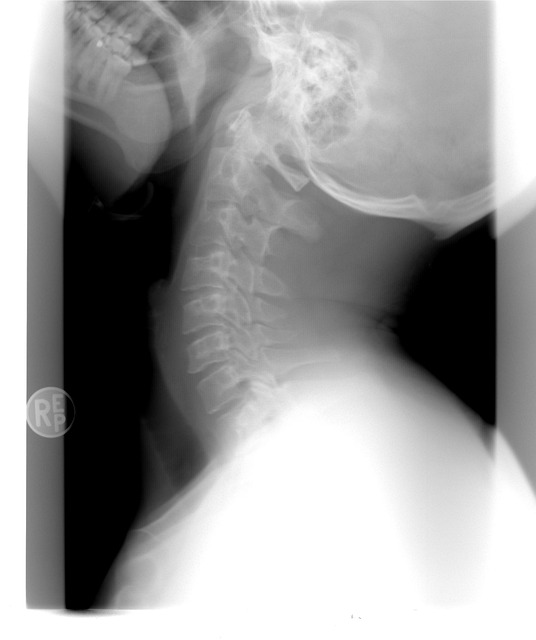

- X-레이: 뼈의 구조와 정렬 상태를 확인